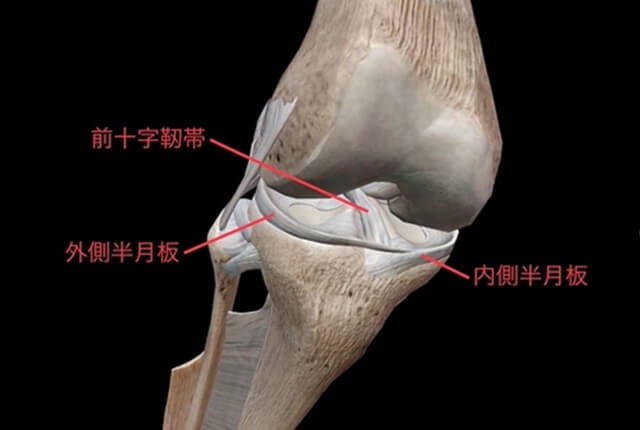

前十字靭帯(ACL)は大腿骨と脛骨をつなぐ靱帯で、後十字靭帯と交差する様に前方に存在します。

半月板は大腿骨と脛骨の間にある線維軟骨です。内側半月板と外側半月板があり、C型の形状をしています。